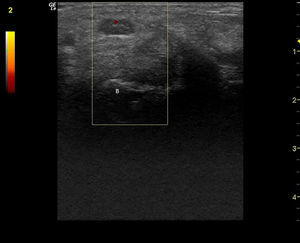

Observación clínicaMujer de 84 años, hipertensa controlada, presentaba desde hace 2 meses lesiones cutáneas en ambas manos de tipo vasculítico asociadas a cianosis del 1.er, 2.° y 3.° dedos, y a dolor intenso que motivaron hospitalización en urgencia por sospecha de vasculitis sistémica. En la anamnesis dirigida, no había elementos de conectivopatía ni consumo de drogas. Recibía enalapril para tratar su hipertensión arterial. En el examen físico destacaban lesiones periungueales, en pulpejos, indicativas de vasculitis, pero llamaba la atención su distribución dermatómica, la severa hipoestesia asociada en el mismo territorio y la importante atrofia de la eminencia tenar, de manera bilateral (fig. 1). El resto del examen era normal; en particular, no había lesiones cutáneas en otras localizaciones y su tensión arterial era normal. Se realizó estudio: hemograma y velocidad eritrocitaria de sedimentación normales, función renal y orina completa normales, factor reumatoideo negativo, anticuerpos antinucleares negativos, perfil ENA detallado negativo, ANCA c y p negativos. La paciente refería de alteraciones de la sensibilidad con parestesias nocturnas y falta de fuerza en manos con tiempo de evolución prolongado, por lo que ya había consultado. Se había hecho el diagnóstico de STC, realizándose una electromiografía de extremidades superiores un año antes. Esta mostraba ya un severo atrapamiento de ambos nervios medianos a nivel de los túneles carpianos, con denervación completa de las eminencias tenares. Se realizó estudio ultrasonográfico de la paciente evidenciando a la entrada del túnel a nivel del pisiforme, un nervio mediano derecho de 17mm2 de área (normal=± 10mm2)1,2 (fig. 2), con presencia central de una arteria mediana remanente (fig. 3). El nervio mediano izquierdo estaba también engrosado, con un área nivel del pisiforme de 18mm2. Ambos nervios aparecían atrapados en el túnel carpiano en los cortes longitudinales (fig. 4).

Corte transversal del nervio mediano en el túnel carpiano: arteria mediana remanente. (Imagen obtenida con ecógrafo General Electrics LOGIC e, con un transductor linear de 8-12 mHz, usando el Doppler de potencia con una frecuencia de 5,0MHz, ganancia de 12, PRF DE 1,2 hHz y filtro de pared de 180Hz).